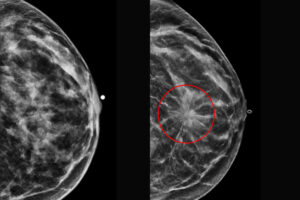

Why is 3D Mammography known as DBT?

3D mammography is also known as Digital Breast Tomosynthesis (DBT), because it takes multiple X-ray images of breast diverse angles. This method allows radiologists to examine breast tissue as one slice at a time. The computer then rebuilds these images into a three-dimensional view. Problem of coinciding structures that can obscure tumors.

- DBT enhances cancer detection rates, particularly for invasive cancers.

- DBT creates a thin slice of the image, reducing overlap tissue.

- DBT detection is most effective for women with dense breast tissue.